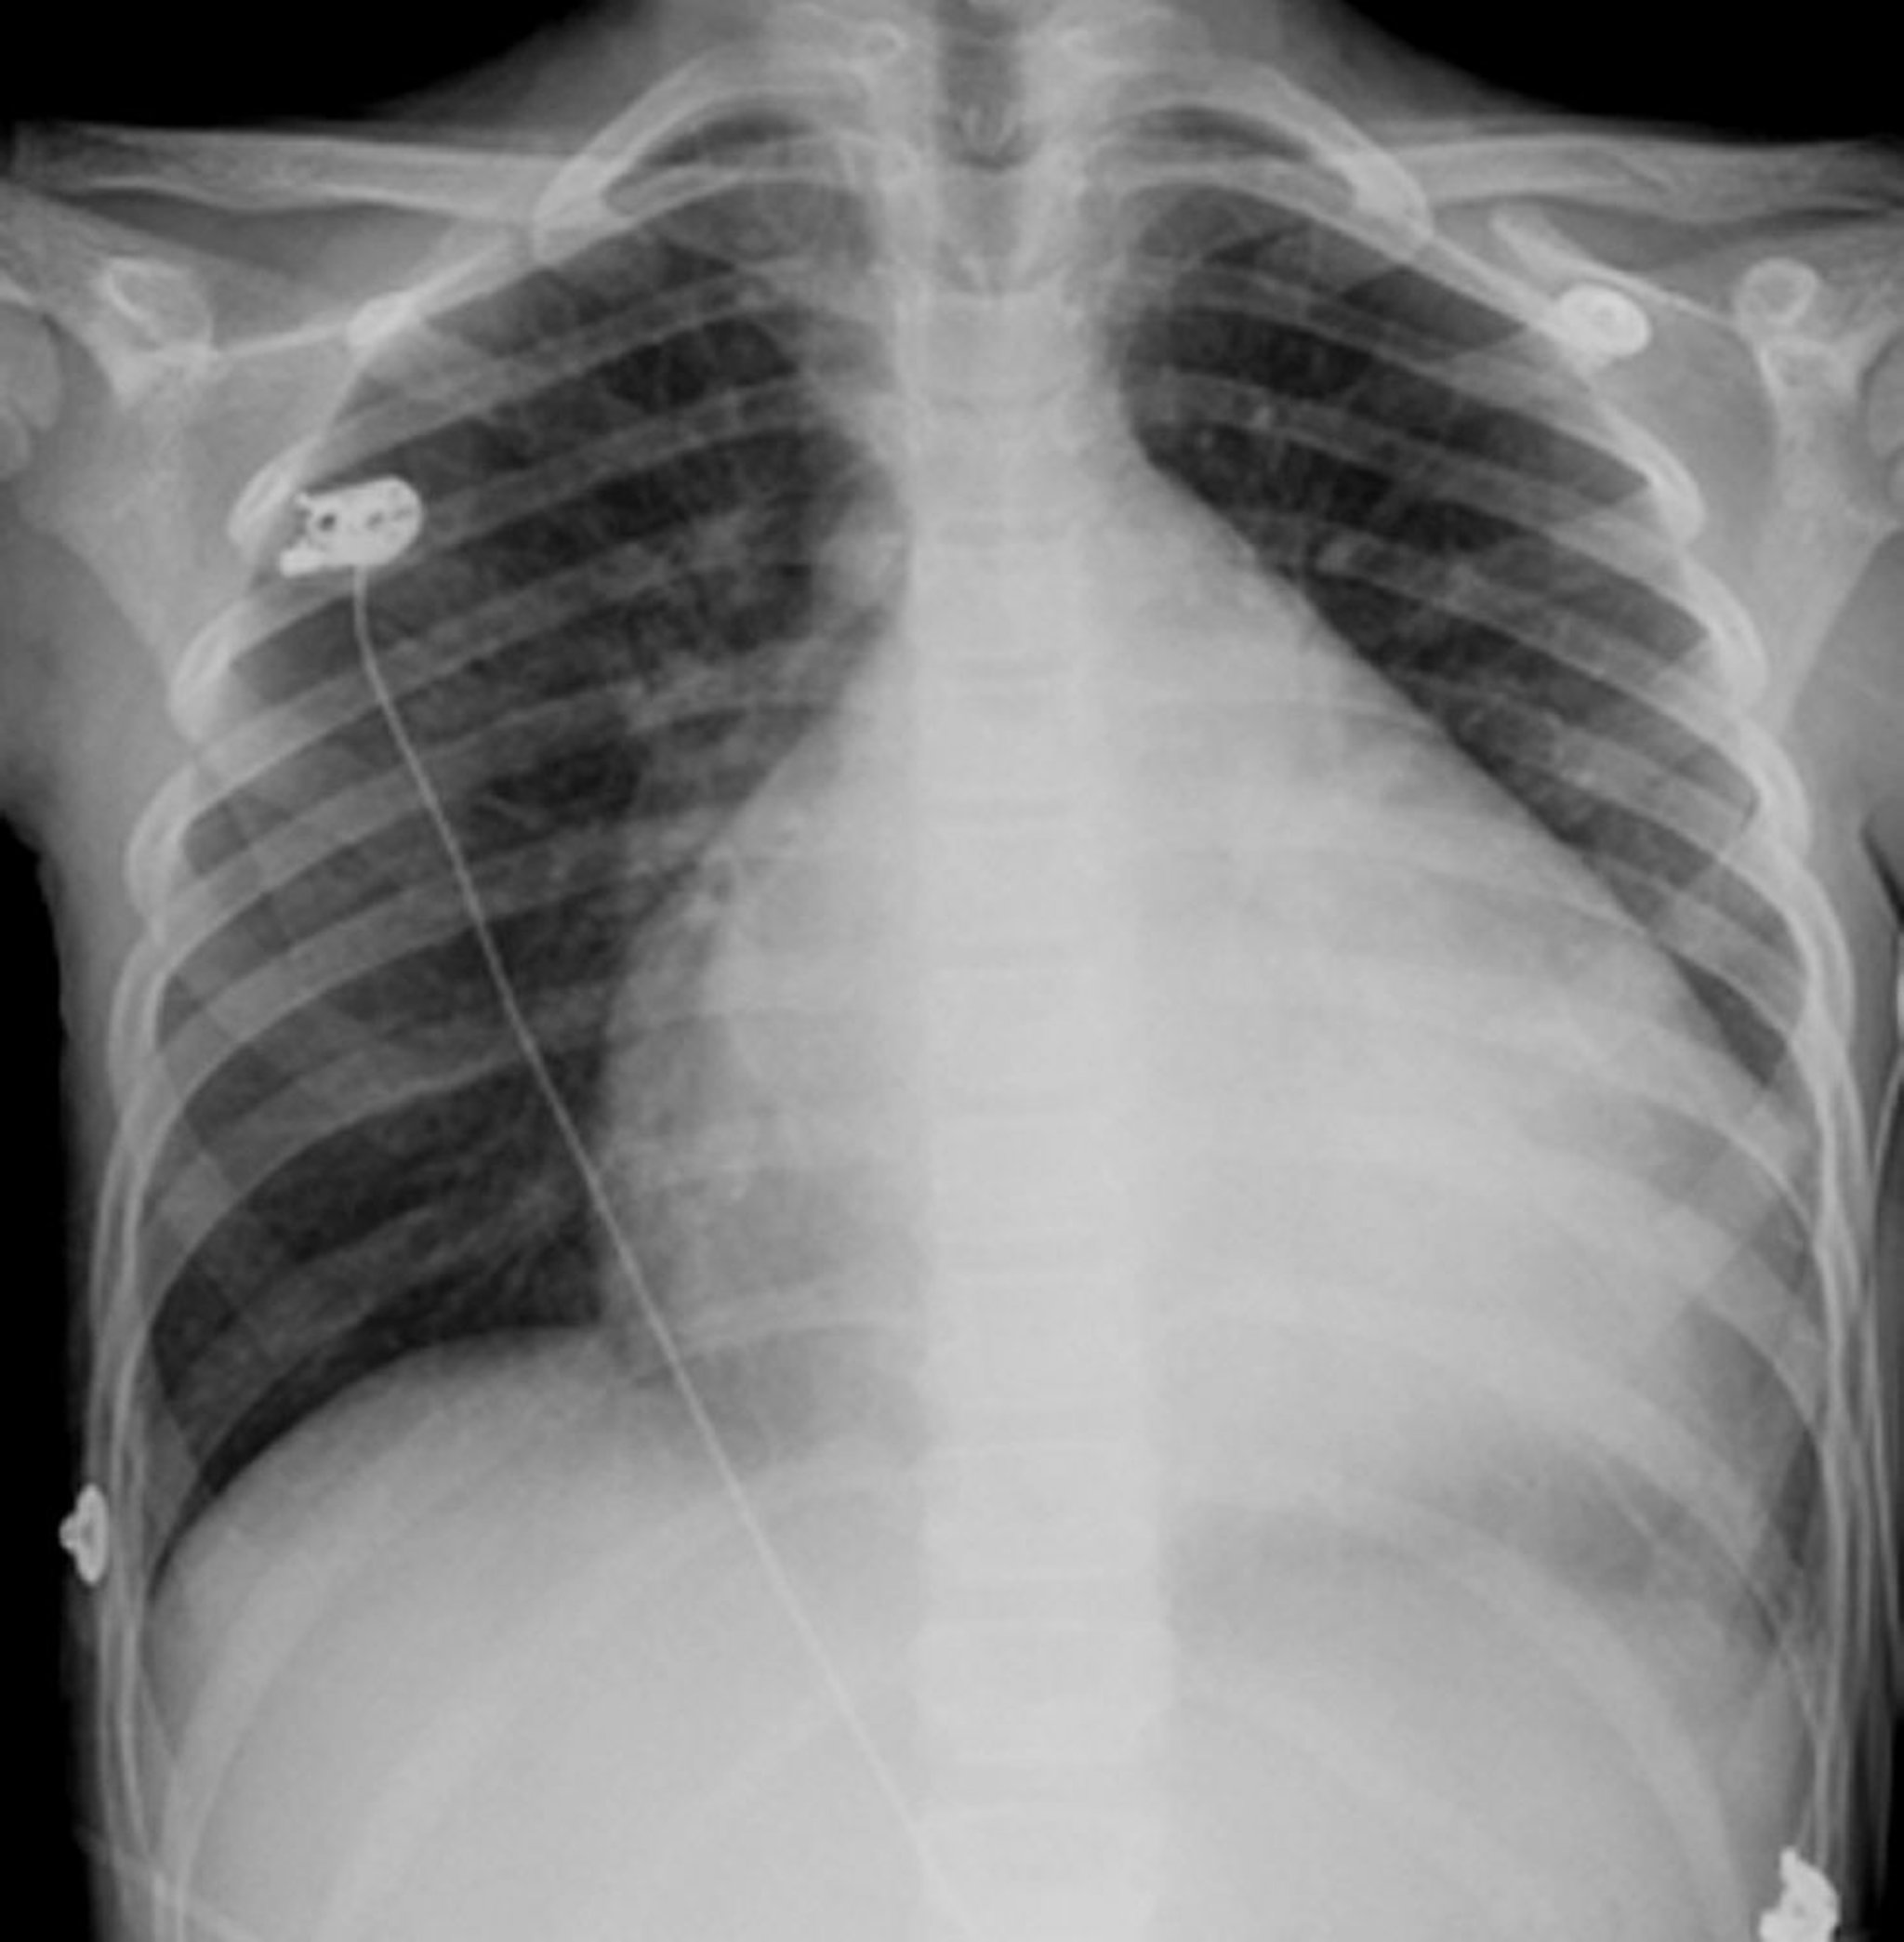

Dilatative Kardiomyopathie (Röntgenthorax)

Diese Röntgenaufnahme zeigt eine schwere Kardiomegalie bei einem Patienten mit dilatativer Kardiomyopathie.